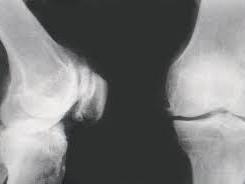

增生性骨关节病是指由于关节退行性变,以致关节软骨被破坏而引起的慢性关节病。又称退化性关节炎、骨关节炎及肥大性关节炎等。